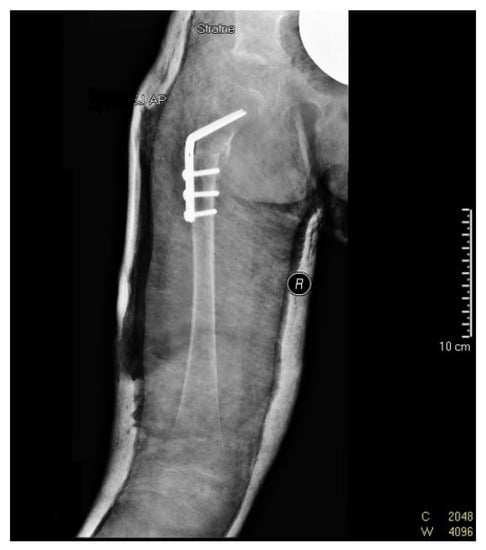

Over time, the parents noticed that the child was very slow to develop motor skills: sitting down and walking. The child did not learn to walk until 22 months of age. While climbing on a slide, the girl always used her lower left limb, without alternating her gait. While walking, she limped on her right lower limb, and reported “right leg pain”. With these observations, the parents again reported to the attending physician, an employee of a private ultrasound lab and national preluxation clinic. Due to the child’s age (24 months), an X-ray of the pelvis was performed, indicating dislocation of the right hip joint (Figure 3).

Figure 3. X-ray scan showing right hip dislocation in the girl (at 2 years of age).